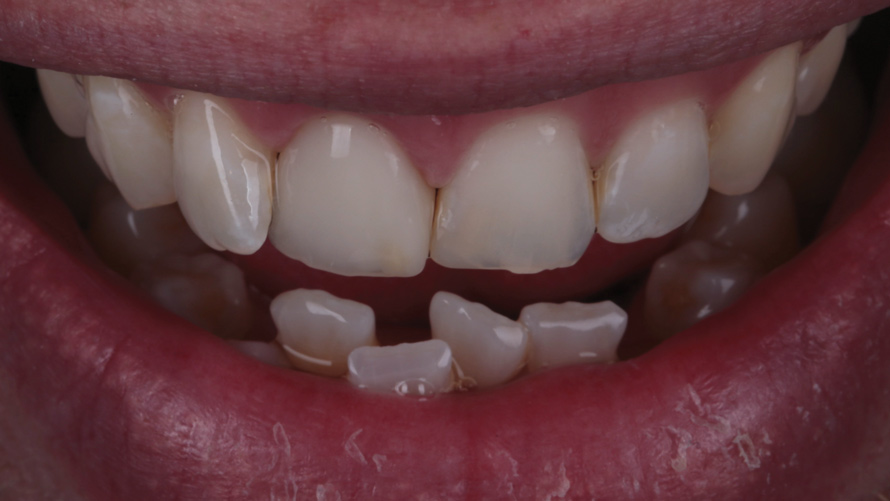

Two patients presented separately to the clinic for the elective replacement of an asymptomatic, discolored, full-coverage restoration on a single maxillary central incisor. The chief complaints of each patient were based solely on esthetics (Figure 1 and Figure 2). During the intraoral examination of each tooth, both patients demonstrated an unremarkable occlusion, good oral hygiene, firm gingiva, probing depths of 2 mm to 3 mm, no bleeding within the sulcus, and tooth mobility that was within normal limits. The results of all sensitivity tests, which included cold, percussion, and palpation, were negative.

(1.) Case 1: Patient presentation of an asymptomatic, unesthetic full-coverage ceramic restoration on the maxillary right central incisor.

Figure 1